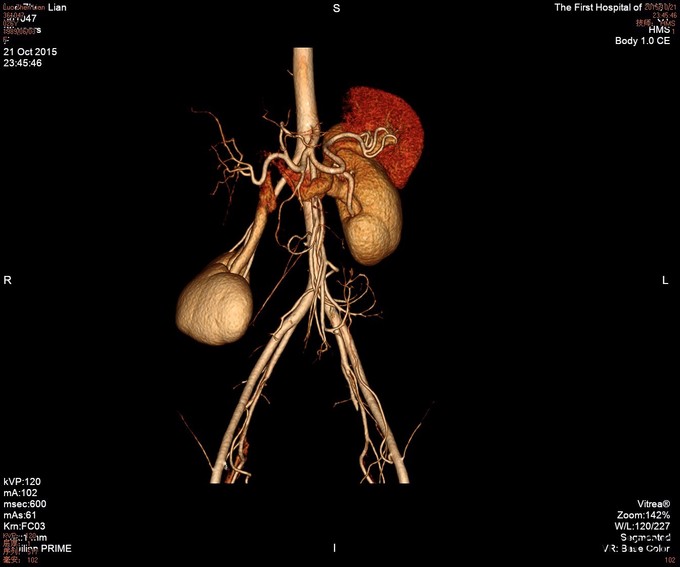

26岁女性患者,13小时前进食大枣后出现腹痛,较为剧烈,左侧腹部为主,5小时前至我院急诊,行腹部CT考虑肠系膜扭转,由急诊收入我科。3年前因胃溃疡出血行胃大部切除术,一月前行内镜下胃息肉切除术。

查体: 患者呈急性痛苦面容,被动屈曲卧位,查体不甚合作,左下腹可见包块样隆起,肠鸣音微弱,局部板状腹、压痛、反跳痛明显,肛门指检未见明显异常。 辅查: 腹部增强CT :1.考虑肠系膜扭转,并肠系膜少许渗出,肠系膜区多发肿大淋巴结。 2.肝脏增大,右肾下移。 3.盆腔少量积液。

诊断:1.肠系膜扭转 2.胃大部切除术后 治疗:完善术前检查,急诊行剖腹探查+行肠系膜旋转复位 ,术后恢复良好,暂无手术相关并发症出现。